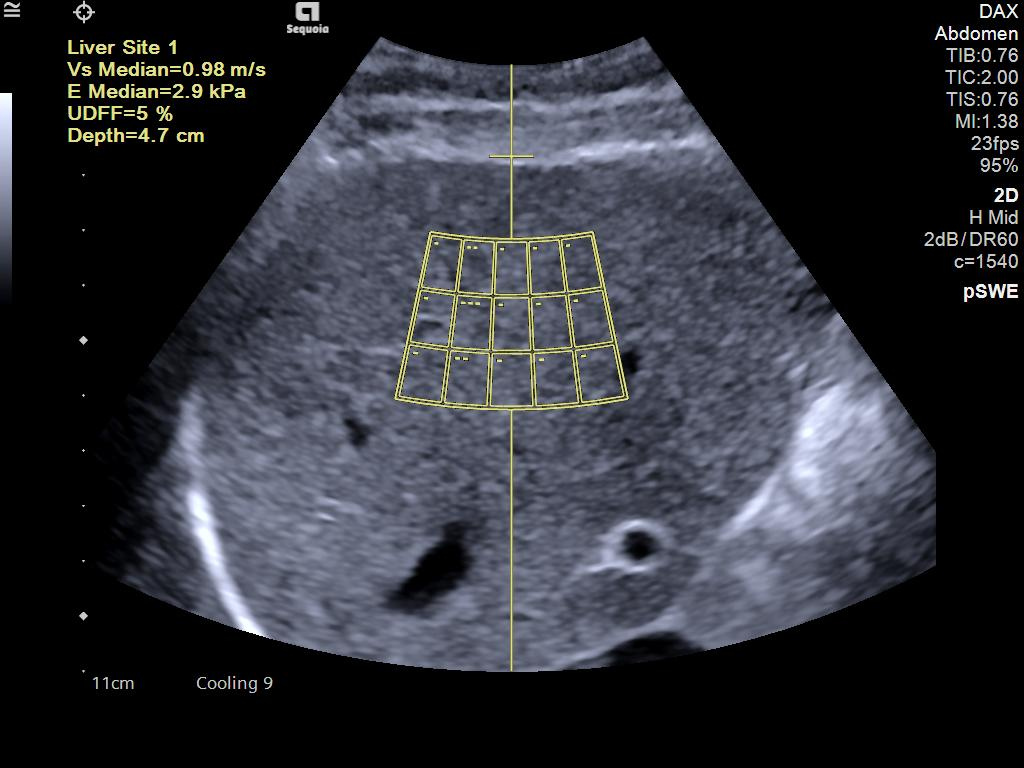

- Ultrasound Derived Fat Fraction (UDFF) for quantitative ultrasound for liver disease assessment.

- Auto pSWE to reduce liver elastography exam time by up to 75%*.